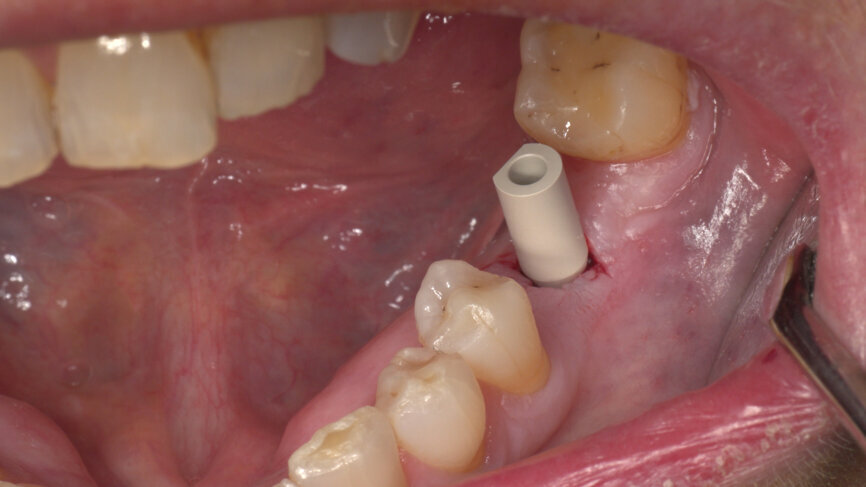

Under local anaesthesia, a flapless implant surgery technique was performed in position #36. Owing to the quality of the bone, staged drilling with continuous saline irrigation was performed in order to obtain a proper, safe insertion torque (Figs. 2–7). One implant (BLT, Regular Neck, Roxolid, ⌀ 4.8 × 10.0 mm) was placed, and a torque of 42 N cm was applied (Figs. 8–11).